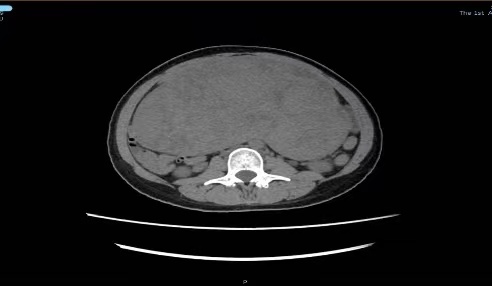

“未见其人,先见其腹”!体重50公斤的黄女士来暨南大学附属第一医院就诊时,她的肚子却巨大得异常突兀,经过全腹CT检查,结果显示:腹盆腔内见一巨大软组织肿块影,大小约22cm×10cm×28cm。子宫后发盆腹腔探及一实性光团,考虑盆腹腔巨大实性占位病变。抽血检查显示,包括肿瘤标记物均正常。

术前CT检查现实腹腔内有巨大肿物